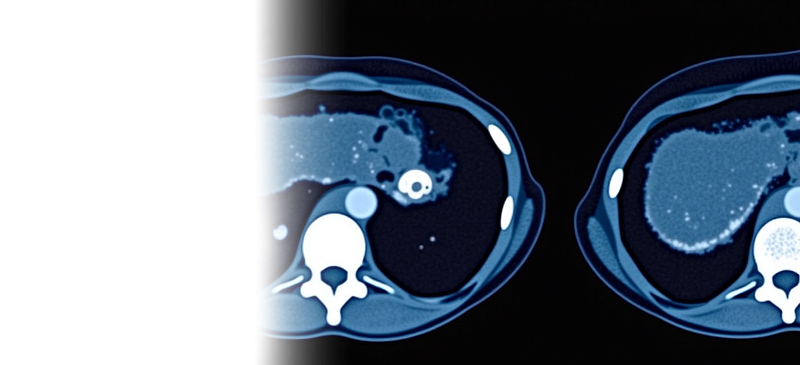

Компьютерная томография брюшной полости и забрюшинного пространства с контрастированием – важный метод исследования органов брюшной полости, включая как паренхиматозные, так и полые, а также органов забрюшинного пространства с введением йодсодержащего контрастного препарата.

Пациенту внутривенно вводится контрастное вещество, которое обеспечивает более качественную видимость органов на получаемых снимках, что позволяет выявить даже самые незначительные изменения в исследуемой области.